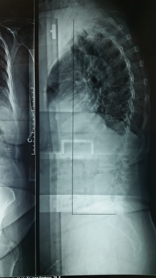

Nos dois planos, fronta e sagital, a linha de prumo deve passar pelo centro da cabeça e da bacia.

Linha de prumo normal da coluna, observe que esta linha deve passar próximo da borda posterior de S1.

Observe este paciente com Escoliose Degenerativa com Flat/Back.

Ele apresente alteração do prumo tanto no plano sagital quanto no coronal decorrente de perda de altura discal e retificação da lordose lombar. Esta deformidade, comum em pacientes idosos, é grave e leva a perda na qualidade de vida e incapacidade funcional, por dor e fadiga muscular.